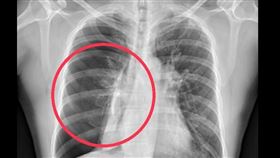

胸痛勿輕忽! 圖解氣胸5大成因一次搞懂

台中27歲簡先生身材高瘦,擁有總讓旁人羨煞吃不胖的體...